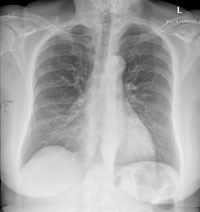

Radiologie Quiz 42

Eine 69-jährige Patientin klagt über einen seit mehr als 4 Wochen anhaltenden Husten mit wenig Auswurf. Die Frage nach Dyspnoe wird verneint. Fieber besteht keines.

Die körperliche Untersuchung ist unergiebig. Der behandelnde Arzt hat aufgrund der Raucheranamnese und des nicht enden wollenden Hustens ein Röntgenbild gemacht:

Thorax pa

Welche Befunde fallen auf (mehrere richtige Antworten möglich)?

Wie beurteilen Sie nun das Röntgenbild?